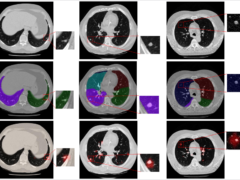

Exploring synthetic datasets for computer-aideddetection: a case study using phantom scan datafor enhanced lung nodule false positive reduction

Purpose Synthetic datasets hold the potential to offer cost-effective alternatives to clinical data, ensuring privacy protections and potentially addressing biases in clinical data. We present a method leveraging such datasets...

Training CADe algorithms with synthetic datasets: augmenting clinical data for improved lung nodule detection

Synthetic datasets hold the potential to serve as cost-effective alternatives to clinical data, potentially aiding in mitigating the biases in clinical data. This paper presents a novel method that utilizes...